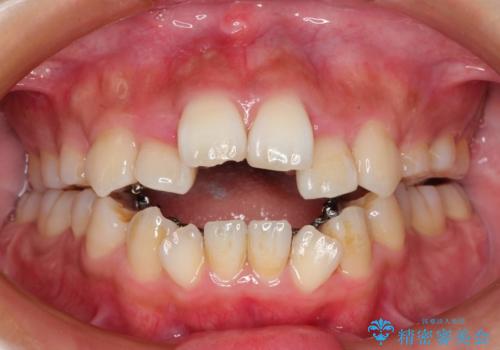

人生が変わる 困難を極める咬合状態に歯列矯正単独で挑戦する

シビアな叢生や開咬も改善することができ、想像以上の改善に時間をかけた甲斐があったと満足していただけました。